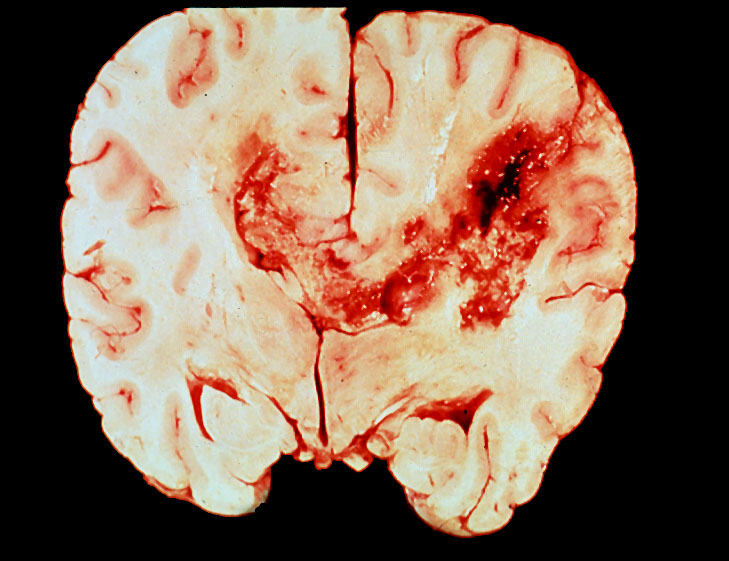

Brain, gross, "butterfly" glioblastoma

So-called "butterfly" glioblastoma multiforme of the corpus callosum. These tumors are inoperable and usually are fatal within a year or so.